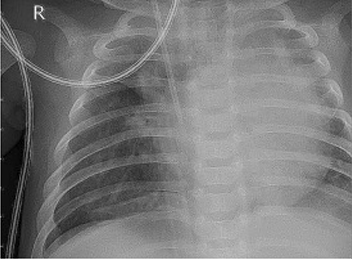

Table 6 Fused image output.

From: Multimodal medical image fusion combining saliency perception and generative adversarial network